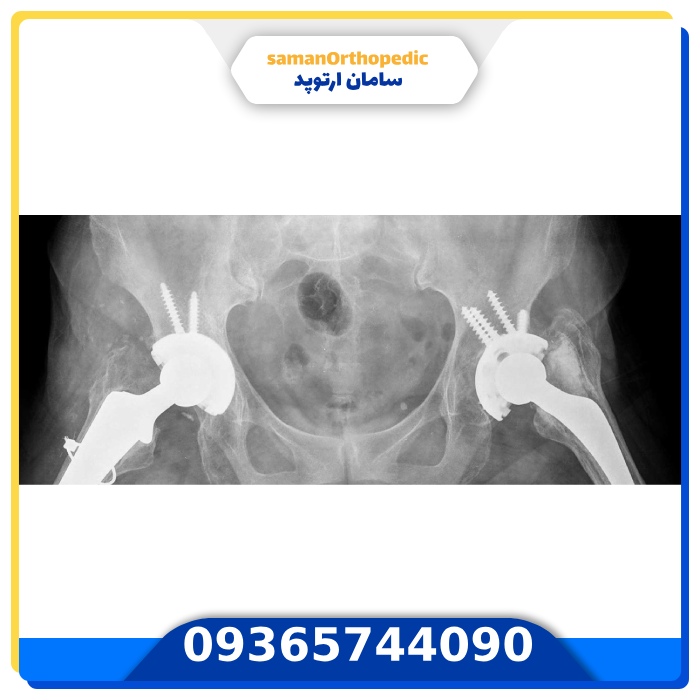

عمل جراحی تعویض مفصل لگن (آرتروپلاستی لگن) | راهنمای جامع 1405 برای بیماران عزیز

درد لگن میتواند انجام سادهترین کارهای روزمره را سخت و طاقتفرسا کند. تعویض مفصل لگن (آرتروپلاستی ران) یکی از موفقترین و مطمئنترین راهکارهای پزشکی است که به بازگرداندن حرکت طبیعی و زندگی بدون درد کمک میکند. در این مقاله با مراحل جراحی، مزایا، مراقبتهای بعد از عمل و نکات کاربردی آشنا خواهید شد. 📞 همین […]

پروتز لگن + راهنمای کامل بیمارن | چطور پروتز لگن کیفیت حرکت و زندگی را بهبود میدهد؟

پروتز لگن یا همان پروتز مفصل لگن، یکی از رایجترین روشهای درمانی در حوزه ارتوپدی است که برای بهبود عملکرد مفصل ران و کاهش درد ناشی از آسیبدیدگیهای شدید یا آرتروز پیشرفته استفاده میشود. این روش که بهنام ارتوپلاستی مفصل ران و لگن نیز شناخته میشود، شامل جایگزینی مفصل طبیعی با یک پروتز مصنوعی است. […]

عمل جراحی تعویض مجدد مفصل لگن | وقتی پروتز قدیمی میگوید وقت رفتن است!

گاهی مفصل لگن پس از عمل اولیه دچار درد، سایش یا مشکلات عملکردی میشود. در چنین شرایطی، تعویض مجدد مفصل لگن راهکاری برای بازگرداندن حرکت، کاهش درد و بهبود کیفیت زندگی است. طبیعی است که بسیاری نگران باشند و بپرسند: آیا عمل مجدد لگن خطرناک است؟ این عمل با تکنیکهای پیشرفته و پروتزهای جدید انجام […]

عمل جراحی تعویض مفصل لگن

اگر در فکر انجام جراحی تعویض مفصل لگن هستید، توصیه میکنیم قبل از هرگونه اقدام، با پزشکان ما تماس بگیرید (09106063586) و از تجربه و مشاوره تخصصی آنها استفاده نمایید. در ادامه پاسخ سوالات رایج شما آورده شده است. از A تا Z جراحی تعویض مفصل لگن رو اینجا بخونید؛ جامع و قابلاعتماد ✔ هزینه، […]